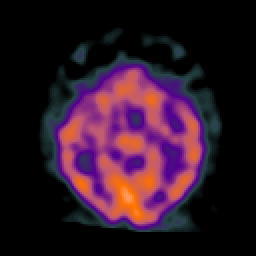

AIDS dementia: overlay -- Slice #7

[Home][Help][Clinical][Tour 1] Slice 7